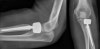

요골두의 분쇄 골절이 관찰됩니다.

X-ray : 전완부 골간막 손상(Essex-Lopresti injury)